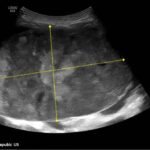

A 5-month-old female presented to the emergency department with worsening abdominal distention and postprandial emesis. Point-of-care ultrasound (POCUS) demonstrated extensive abdominal free fluid with a large, heterogeneous mass in the suprapubic region. This was confirmed on computed tomography (CT) of the abdomen and pelvis. The patient was urgently taken to the operating room for exploratory laparotomy where a ruptured tumor was discovered. The patient was eventually diagnosed with ovarian juvenile granulosa cell tumor. POCUS can be vital in guiding the recognition of rare pediatric conditions in the emergency department and should be considered in patients where there is concern for an acute abdomen.